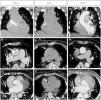

Thin (3 mm) maximal intensity projection reconstructions in coronal (first row) and transverse planes (second and third rows) of the multidetector chest CT scan performed on the first day (Panels A, B, C), on the second day (panels D, E, F) and one week later (Panels G, H, I), showing how the ascending aortic dissection and RCA occlusion and reperfusion evolved.

Left CA showed no coronary disease. After the first contrast injection in the right coronary artery (RCA)—which also excluded disease—a radiopaque area was seen in the aortic wall, suggesting catheter-induced (iatrogenic) ascending aortic dissection (IAD) (Figure 1, Panel A, arrow). A few minutes later, occlusion of RCA occurred as a result of dissection progression (Figure 1, Panel B, arrow). CT angiography (CTA) performed immediately in the hemodynamics laboratory (same room, moving gantry) confirmed IAD dissection and acute occlusion of the RCA (Figure 2A, B and C, arrows). Angioplasty of RCA was tried without success because it was not possible to catheterize the true lumen. Bedside echocardiogram showed mild depression of global systolic function of the left ventricle with akinesia of the inferior wall and hypokinesia of the free wall of the right ventricle. As percutaneous intervention was not possible, the patient was referred for coronary artery bypass grafting, but this was refused because of the “location” of the infarction, the relative hemodynamic stability of the patient and the lack of signs of dissection progression. A conservative approach was therefore adopted. The patient developed an inferior myocardial infarction but had a good clinical and hemodynamic recovery. Peak troponin I was 11 ng/mL. One week later, repeat CTA revealed IAD regression (Figure 2G and H, arrows) and spontaneous RCA reperfusion (Figure 2I, arrow).